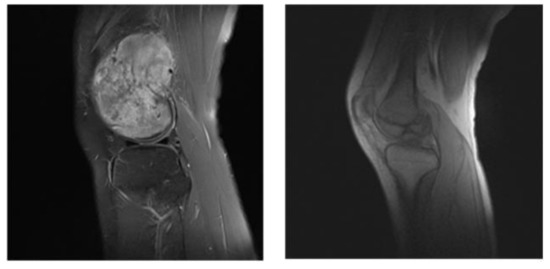

In our segmentation system, before the dataset is trained, we divide the dataset into useful slices (US) and normal slices (NS), as shown in the Figure 7; the tumor location is obvious in the left image, and the boundary between the tumor tissue and the normal area is also very clear. Such pictures will reduce the training burden during the training process, and speed up the training and enhance the accuracy of the model so that it is suitable for input as a training set. As shown in the picture on the right, below, the segmentation boundary between the tumor and other tissues is not obvious. If the input training may make the training process time-consuming and laborious, we divide it into the NS dataset.

Figure 7.

US (the left) and NS (the right) example images.